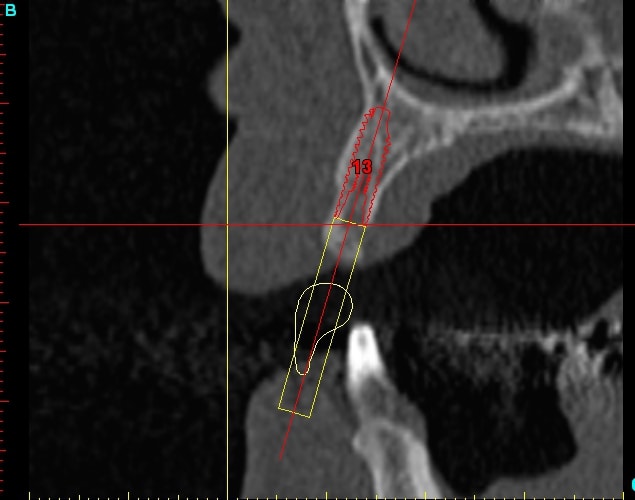

Dar12 dmdcf3 - Eugenol

Dar13 snfr77 - Eugenol

14dar tm9a6n - Eugenol

Dar14 mu6ia0 - Eugenol

15dar srylok - Eugenol

23dar fu8chl - Eugenol

Dar23 cngblb - Eugenol

24dar rfsfid - Eugenol

Dar24 scegbz - Eugenol

25dar yv2tvr - Eugenol

Dar15 gpvqe1 - Eugenol

Dar25 mrwngv - Eugenol

12dar ujxzdu - Eugenol

13dar zaa5vz - Eugenol

22dar mrs1pw - Eugenol

Darcl12.12 - Eugenol